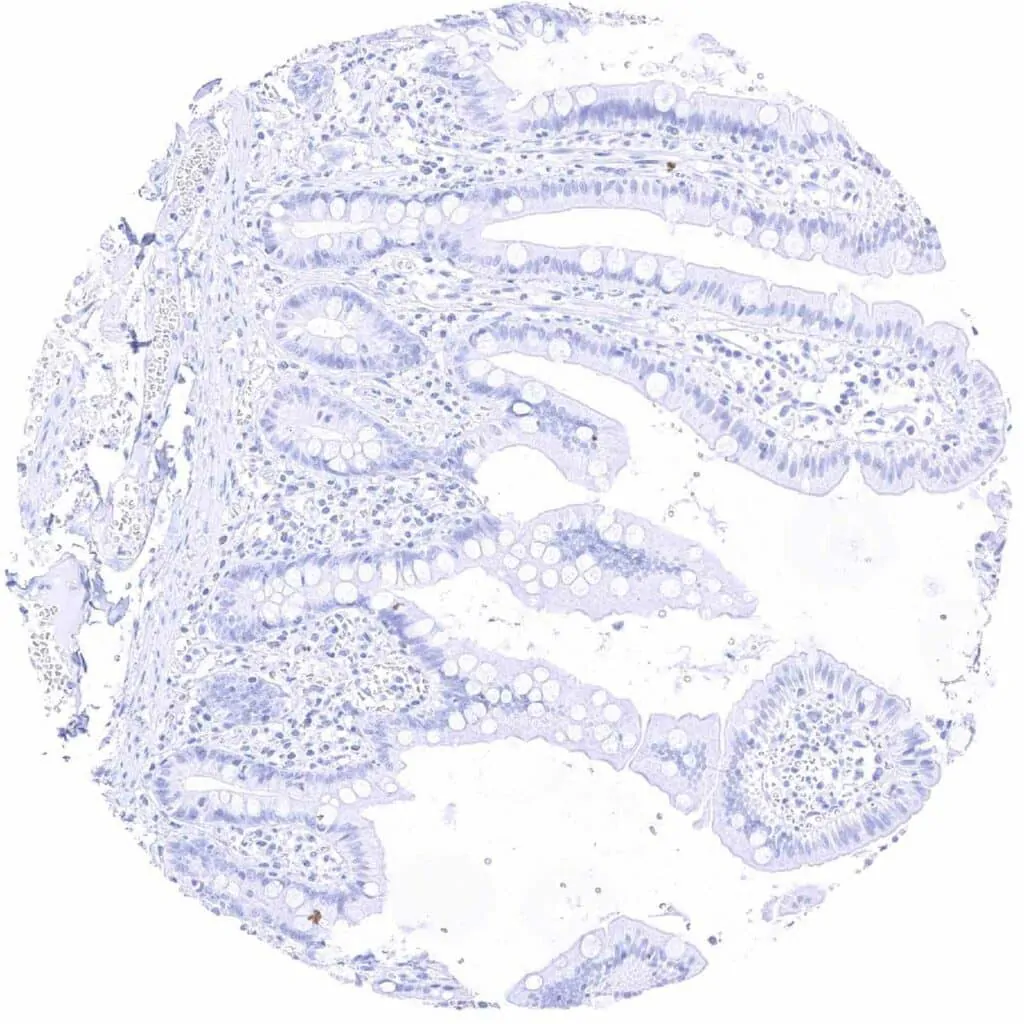

Ileum, mucosa